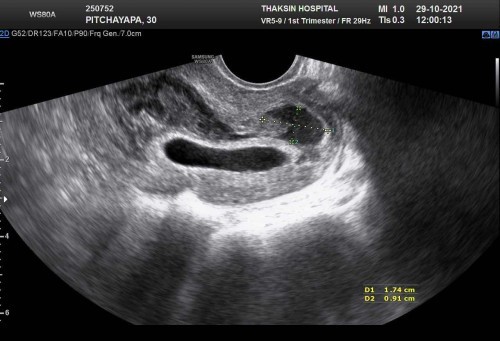

ภาวะแท้งคุกคาม 6 w

ตั้งครรภ์ได้ 6 w เกิดภาวะแท้งคุกคาม เลือดออกเยอะมากคะ แต่คุณหมอบอกน้องหัวใจยังเต้นอยู่ แม่ๆมีวิธีดูแลตัวเอง ลูกในท้อง ยังไงบ้างคะ กับภาวะนี้ #ขอบคุณสำหรับคำตอบค่ะ